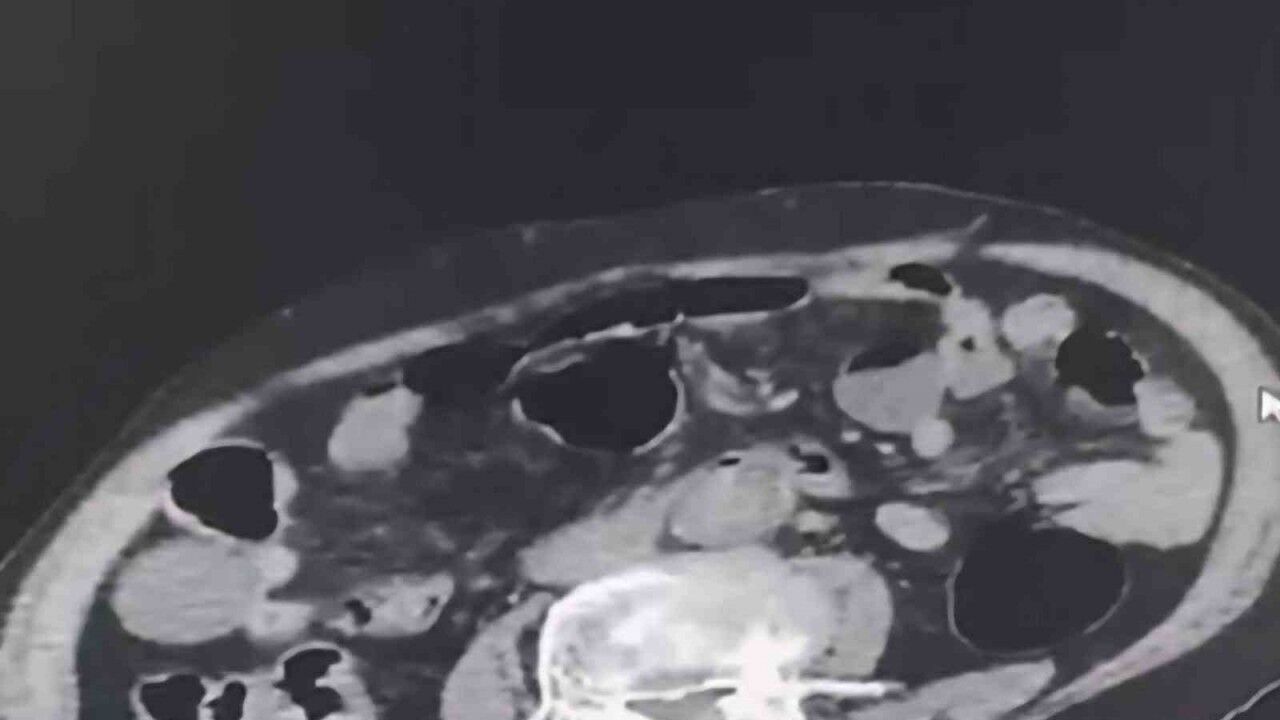

Denizli İl Emniyet Müdürlüğü Narkotik Suçlarla Mücadele Şube Müdürlüğü tarafından uyuşturucu madde ticaretinin önlenmesine yönelik yapılan çalışmalar kapsamında şehir dışından Denizli’ye uyuşturucu sokmak isteyen 2 yabancı uyruklu şahıs takibe takıldı. Takip sonrasında Denizli’de malları teslim edeceği kişi ile buluştukları esnada düzenlene operasyonla 3 şahıs gözaltına alındı. Gözaltına alınan şüpheliler üzerinde yapılan incelemelerde yabancı uyruklu bir şüphelinin uyuşturucu maddeyi cinsel organında taşıdığı belirlendi. Şüphelilerin üzerlerinde ve adreslerinden yapılan aramalarda 6 parça halinde 145 gram metamfetamin maddesi, 260 gram sıvı halde sentetik ecza maddesi ele geçirildi.